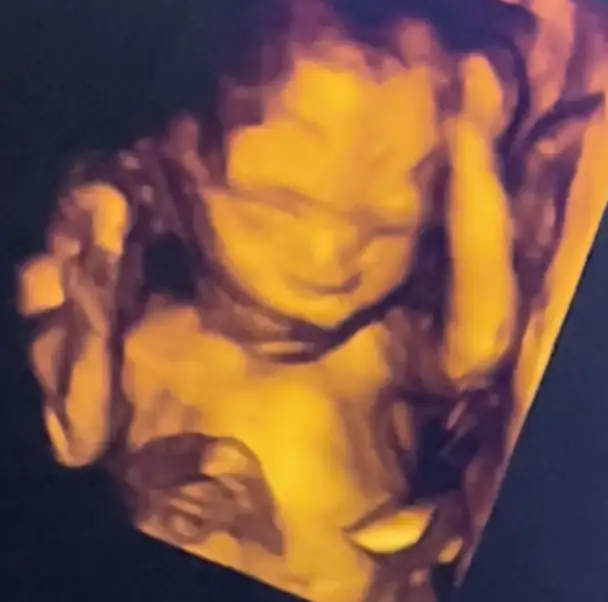

maşallah güzel haberler ile çıkmışsınBugün ayrıntılı ultrasondan cıktım cok sukur her sey cok guzeldiultrasonda kanama alanımıda göremedi bitmiş dedi ,

cok az kahverengiye yakın akıntım oluyor oda çok az kalmıstır o gelıyor olabılır dedi . Bebeğimin böbreklerine kalbine midesine kan akısına baktı her seyin gayet yolunda oldugunu soyledi. Ben normalde bu yasadıgım kanamalar öncesi faktor v heterizigot oldugum için hem coraspin hemde oksapar 4000lik oluyordum, coraspini bıraktırmıştı oksaparıda yarım 2000lik olmaya baslamıstım kan akısı benım için önemliydi sorun cıkmadı cok iyi dedi kan akısınada . Bebeğim 1 hafta onden gidiyor gayet iyi dedi doktor. Rahim seklımın kalp olmasından suphelendiğni soylemıstım bu nedenle rahim agzıda ölçtürüyorum ben hep , vajinal rahim agzımı 40ml ölçtü gayet iyi oldugunu soyledi içim bi rahatladı. Agrılardan bebek toplanmasından bahsettim normal dedi. Normalde vajinal kültürde baksın istiyordum alt karın agrımdan dolayı ,akıntımın sarı oldugundan ama kokusuz ve kasıntısız oldugundan bahsettim sorun yoktur o halde vajinal kültüre gerek olmadıgını soyledi bende üstelemedim bu nedenle . Daha oncede bahsetmiştim baska bir gözde görsün istiyor doktorum bu nedenle 3 hafta sonraya birini önerdi onada randevu alacagım ayrıca.Buda ultrason fotografımız teyzeleri babasına cok benzıyor